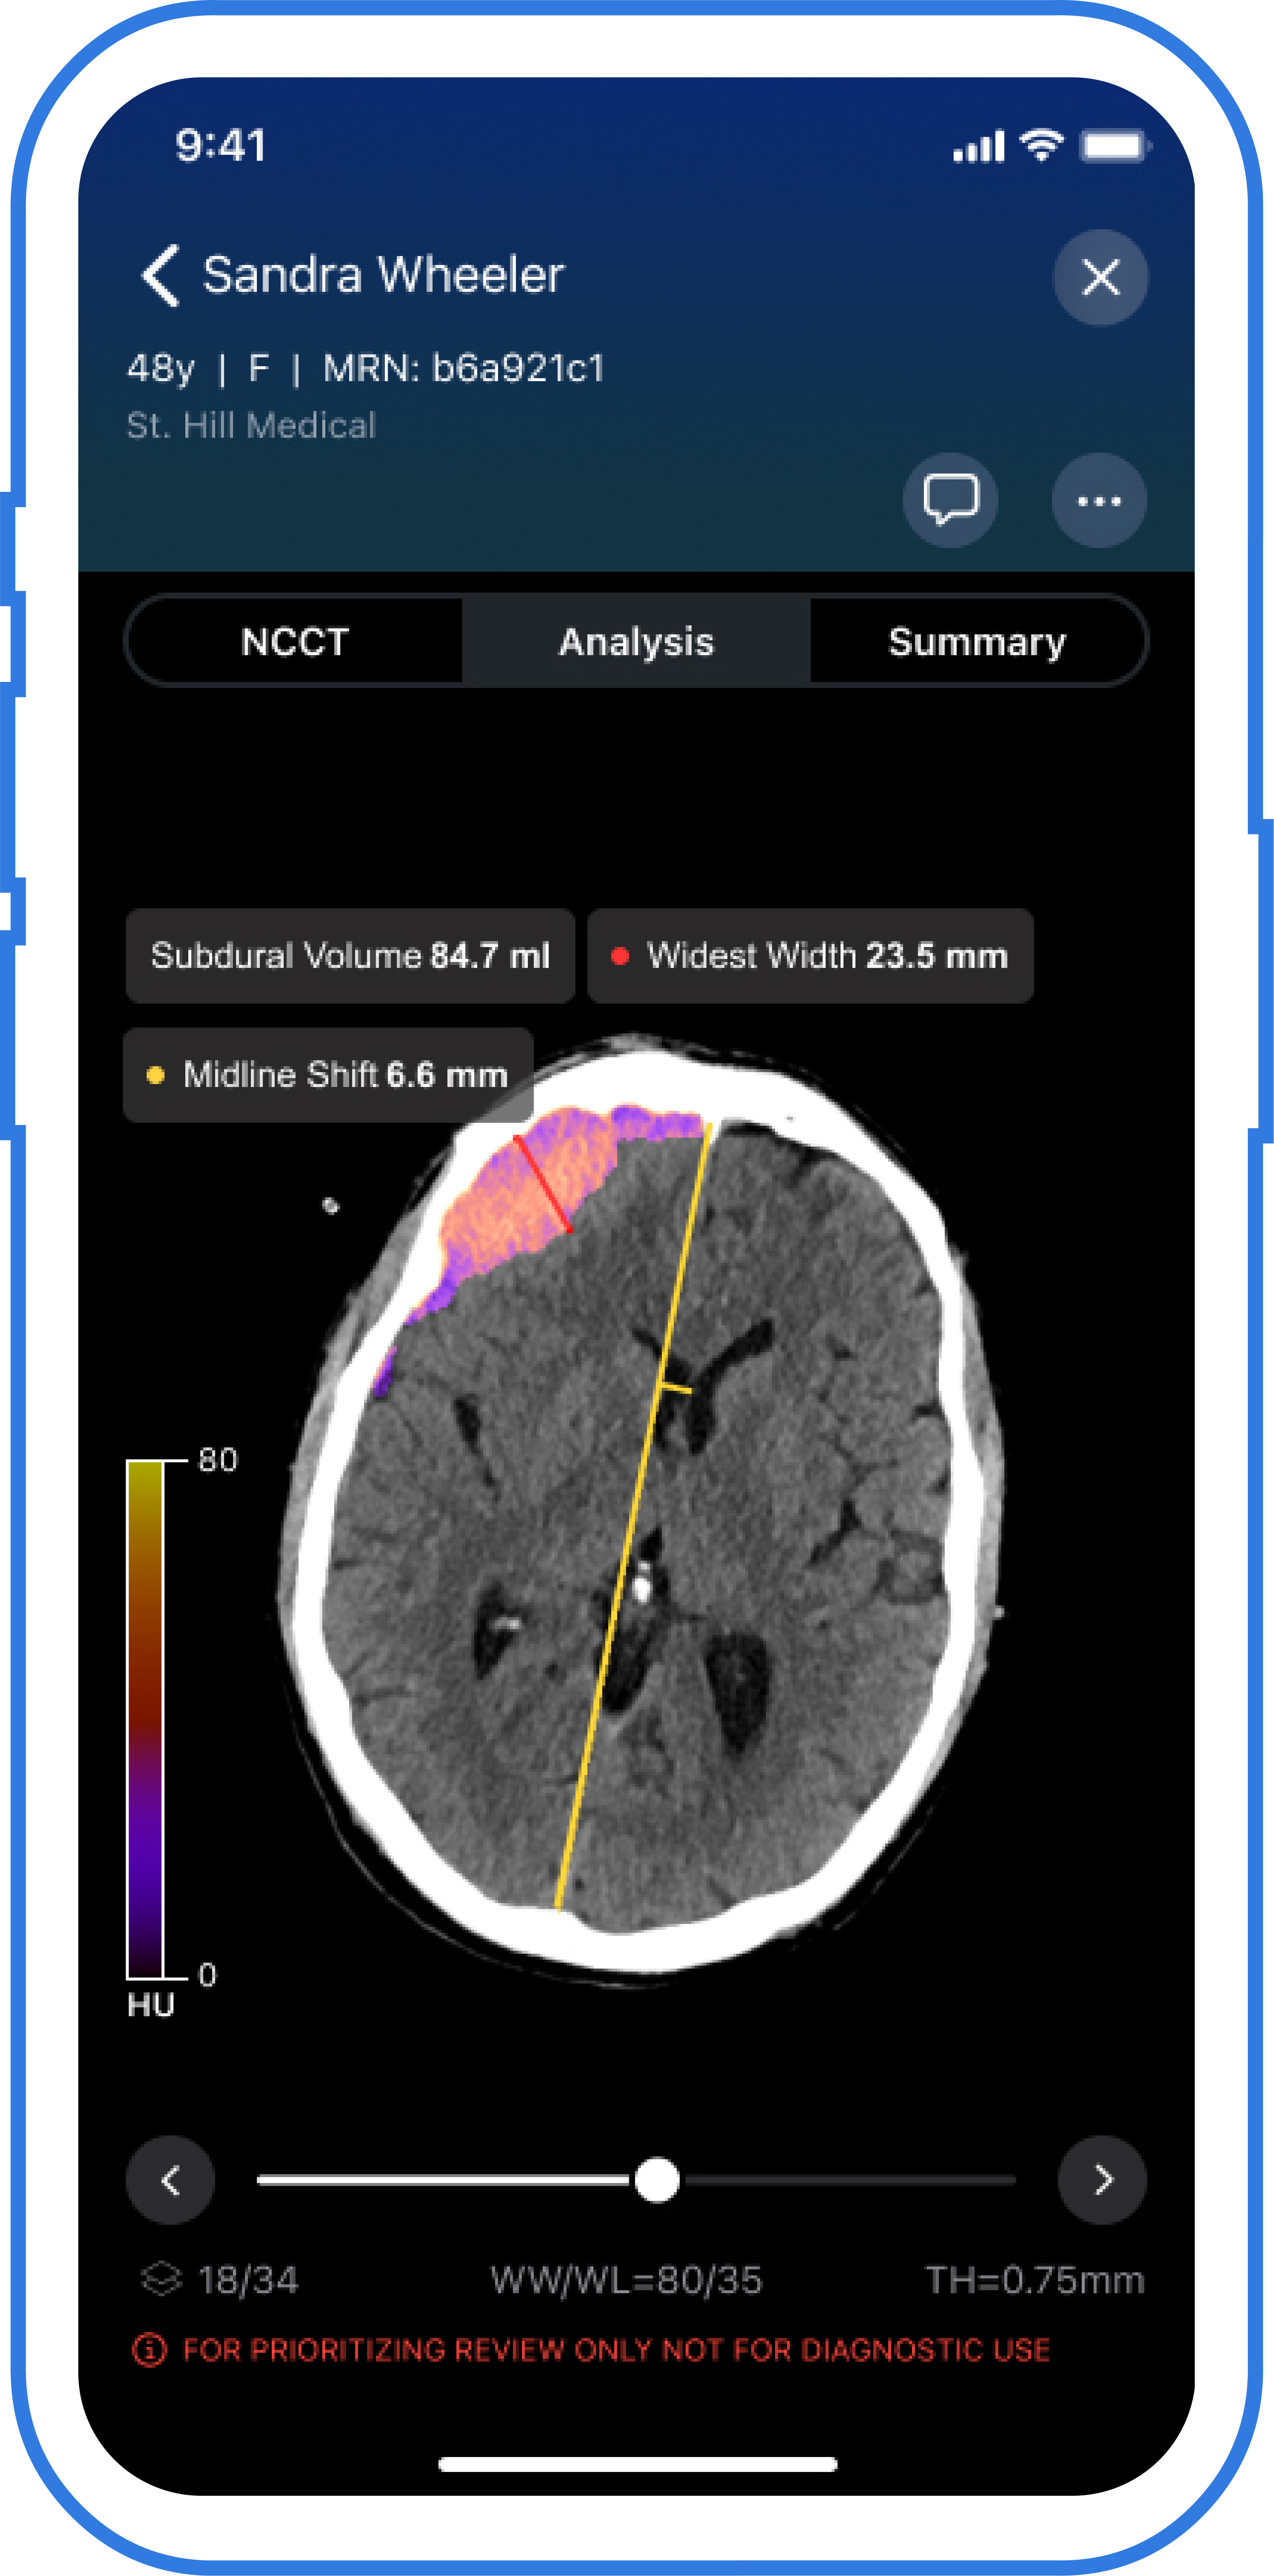

The AI-powered Viz Subdural Plus reportedly provides automated measurements and labeling of subdural collections, including subdural hemorrhages (SDHs), based on non-contrast CT scans.

The Food and Drug Administration (FDA) has granted 510(k) clearance for the artificial intelligence (AI)-enabled software Viz Subdural Plus, which assesses non-contrast computed tomography (NCCT) scans to offer automated quantification of subdural hemorrhages and other subdural collections.